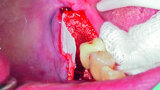

Fig. 6: Facilitation of Schneiderian membrane elevation with a collagenous fleece.